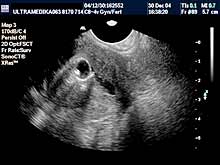

novoformiranih krvnih sudova, ako je došlo do ovulacije. Ova metoda

se naziva folikulometrija. Neadekvatna hormonska aktivnost jajnika

zahteva analize iz krvi radi otkrivanja razloga poremećene funkcije

jajnika. Medikamentna nadoknada, smanjene funkcije jajnika, se

takodje proverava folikulometrijom. Ova stimulacija ovulacije obično

dovodi do ovulacije-sazrevanja jajne ćelije tj određivanja dana u

menstrualnom ciklusu žene kada može doći do začeća. Folikulometrija

određuje vreme započinjanja supstitucione terapije a pregldi

ultrazvukom počinju od 2 ili 5 dana od početka menstruacije (važna

je veličina folikula pre započinjanja terapije da bi stimulacija

bila uspešna).